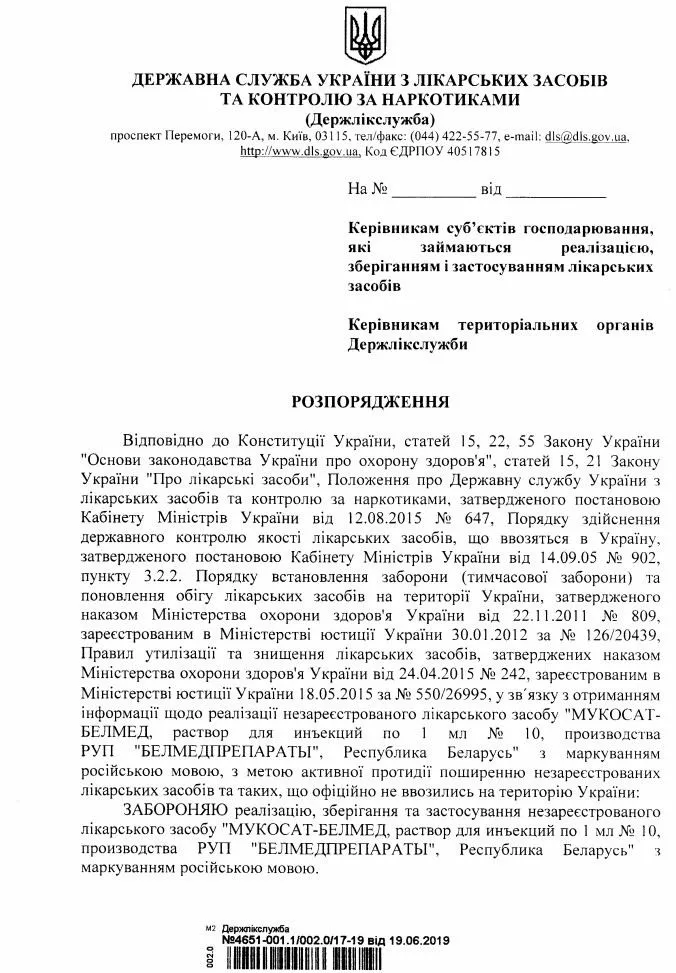

Решение о постоянном запрете ведомство утвердило в среду, 19 июня.

Речь идет о "Мукосат-Белмед", растворе для инъекций по 1 мл № 10 всех серий производства РУП "Белмедпрепараты", Республика Беларусь.

Известно, что лекарства с маркировкой на русском языке не были зарегистрированы в Украине. Поэтому Гослекслужба с целью активного противодействия распространению незарегистрированных лекарственных средств запретила все серии препарата.

В Украине запретили "Мукосат-Белмед" всех серий